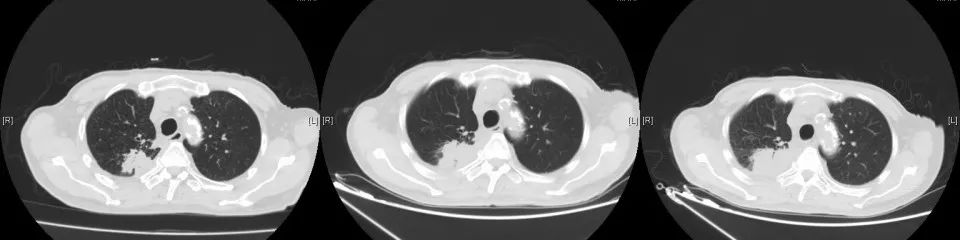

2017年7月行全身PET-CT提示右肺上叶高代谢病灶。2017年8月份行肺穿刺活检未能明确病理诊断。2017年10月份再次行全身PET-CT:右上肺结节增大,代谢增高,与家属商量后,外院予试用口服“吉非替尼”靶向治疗。

2018年1月复查胸部CT:右肺占位较前增大,余无明显特殊不适。外院再次行肺穿刺活检,病理:右肺组织见癌转移(符合膀胱癌肺转移)。2018年3月14-29日于我院行肺转移灶局部放疗。2018年5月15日-7月11日予标准方案化疗2周期。期间病情稳定。2018年10月复查,局部肺转移灶增大进展、且出现肺新转移灶,评估疗效PD,行NGS全基因检测,根据检测结果,即选用阿法替尼口服行靶向治疗。

CT变化: